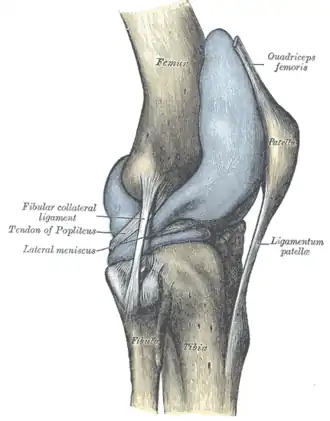

Ligamentos

| ligamento colateral medial ou ligamento colateral tibial (LCM) | fora | epicôndilo medial do fêmur | condilo tibial medial | O Ligamento Colateral Medial protege a parte medial do joelho de ser aberto por uma força aplicada nas laterais do joelho (joelho valgo). |

| ligamento colateral lateral ou ligamento colateral fibular (LCL) | fora | epicôndilo lateral do fêmur | cabeça da fíbula | o Ligamento Colateral Lateral protege as laterais do joelho de uma força dobrante interior (joelho varo). |

| ligamento poplíteo oblíquo | fora | côndilo externo do fémur | continuidade do tendão do semimembranoso | Expansão Tendinosa dos musculo semimembranoso. Fortalece a parte de trás da capsula |

| ligamento poplíteo arqueado | fora | área intercondilar da tíbia côndilo lateral do fêmur a seguir da cabeça fibular | Conecta para a porção medial da cabeça fibular | Este ligamento fortalece o joelho posterolateralmente e quando lesionado está em combinação com uma lesão do tendão PCL e poplítea. |